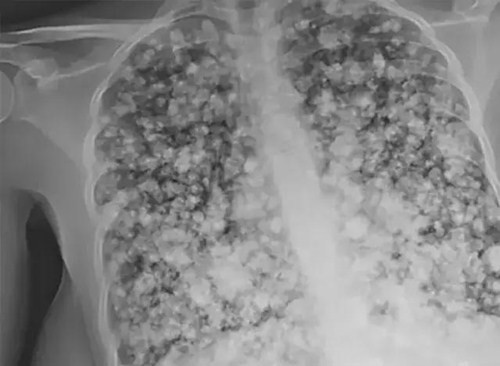

Phương pháp này giúp ổn định tình trạng của thiếu niên nhưng không hề giúp sức khỏe của cậu hồi phục. Phim chụp X-quang cho thấy, phổi của cậu thiếu niên đã trở thành phổi bỏng ngô, một dạng tổn thương phổi cực kỳ nghiêm trọng.

Điều đáng sợ hơn nữa là bác sĩ chẩn đoán phổi của cậu thiếu niên không thể chữa khỏi, chỉ khi được tiến hành ghép hai lá phổi mới có cơ hội phục hồi. Thậm chí nếu ca mổ thành công thì rất có thể, cậu thiếu niên cũng bị rút ngắn tuổi thọ hơn nhiều.

| Tổn thương "phổi bỏng ngô" không thể hồi phục trừ khi có phép màu. |